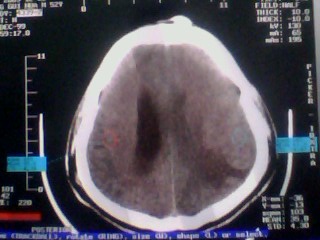

以下是引用随光逐影在2010-1-7 14:49:00的发言:[br]1)结合病史,考虑多发性脑转移瘤可能性大;建议行ct增强扫描检查。2)大脑镰下疝。3)脑积水。